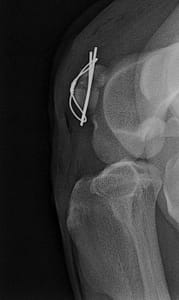

De knieschijf is een onderdeel van het totale kniegewricht en zal bij een fractuur erge artrose veroorzaken. Hieronder kunt u zien dat de knieschijf hersteld is dmv twee pinnen en een draad er omheen. De knie kan weer normaal functioneren en het been weer gestrekt worden. De patient wordt gedurende 6 weken aan de lijn uitgelaten, krijgt pijnstilling en een gewrichtsondersteundend middel mee.